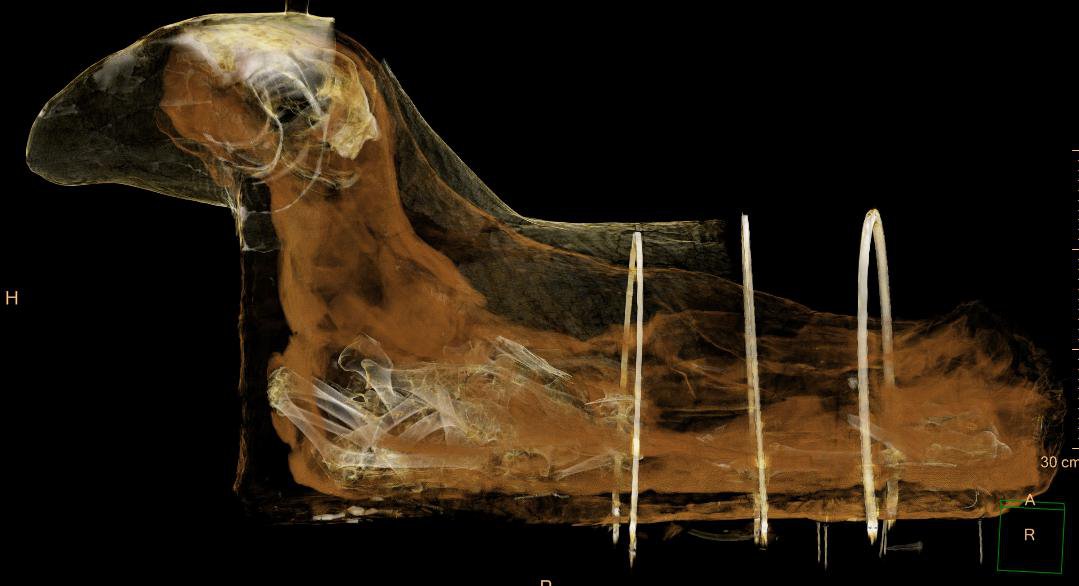

The first stage of the project saw the mummy undergoing a CT scan at one Affidea center in Poland, which allowed scientists to discover a degenerative spinal condition previously undetected in smaller studies, without putting its conservation status at risk.